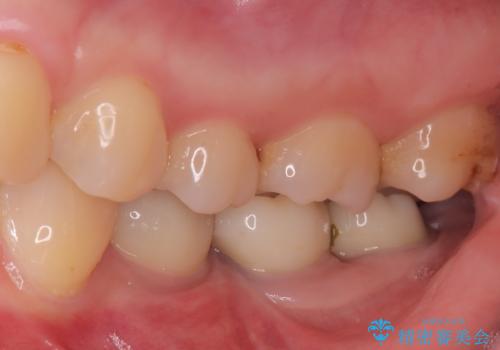

今回の治療では、虫歯の大きさや深さに応じて、異なるセラミック修復法を適用しました。

比較的軽度な虫歯には、セラミックインレー(詰め物)で対応し、健全な歯質を最大限に残しました。

進行した虫歯や歯の強度が低下している歯には、セラミッククラウン(被せ物)を選択し、歯全体を保護することで破折を防ぎました。

短期間での治療を可能にしつつ、天然歯と見分けがつかない審美性と、長期的に安定する機能性を兼ね備えたセラミック修復を実現しました。